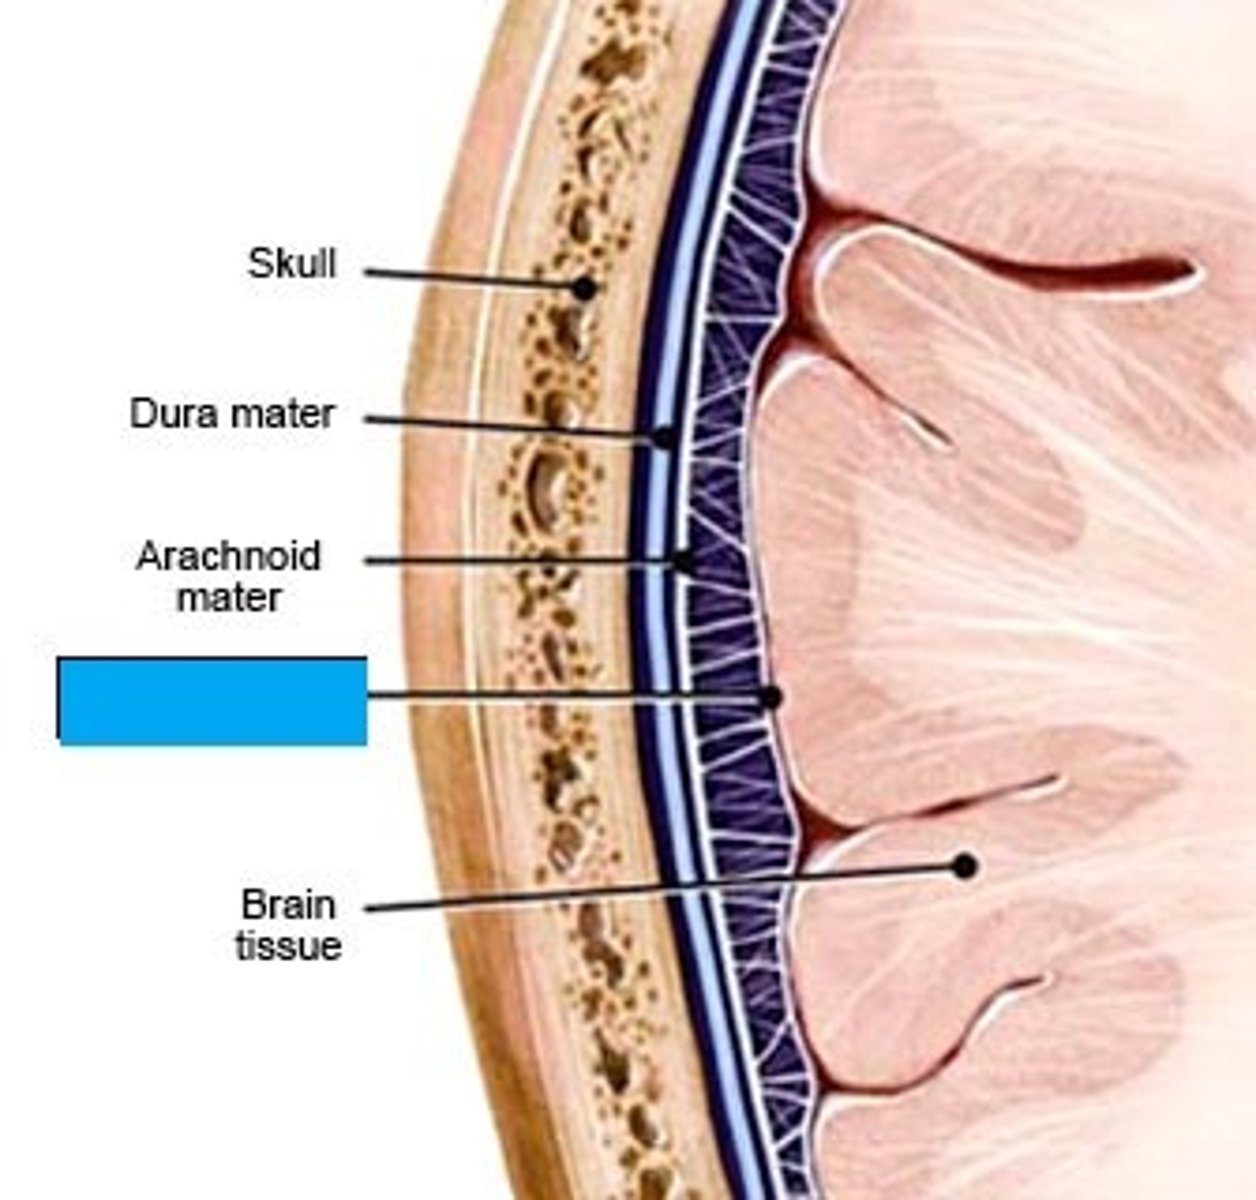

dura mater

periosteal layer

meningeal layer

arachnoid mater

subarachnoid space

with arachnoid trabeculae

pia mater